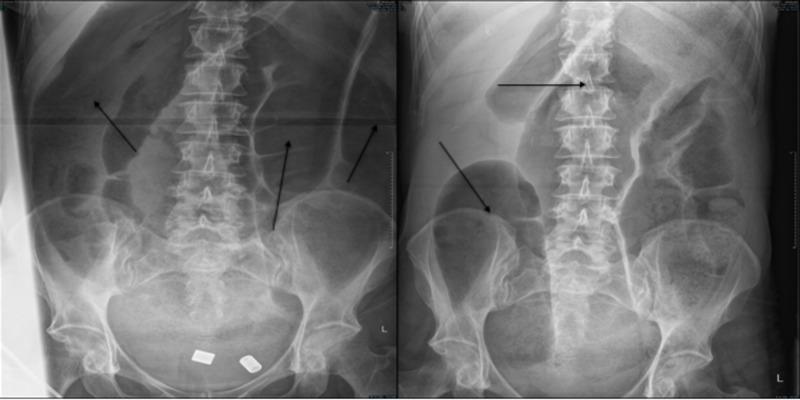

Mitochondrial encephalomyopathy with lactic acidosis and stroke-like symptoms (MELAS) is a rare mitochondrial disorder that typically presents before the age of 40 with most patients diagnosed before the age of 20. Symptoms and signs typically include mitochondrial myopathy, encephalopathy with stroke-like episodes, seizures and/or dementia, and lactic acidosis. We present a case of a 56-year-old lady presenting with recurrent ischaemic strokes and seizures associated with non-territorial low attenuation areas on brain imaging. Together with a raised serum lactate and background history of Syndrome of Inappropriate secretion of Anti-Diuretic Hormone (SIADH), genetic analysis was carried out that confirmed the presence of the most common mutation associated with MELAS syndrome which is m.3243A>G mutation. This case raises the importance of considering a diagnosis of inherited mitochondrial disorder when faced with recurrent atypical stroke-like episodes, when neuro-imaging is inconsistent with ischemic infarction, even in adults or elderly individuals. It also highlights the importance of background history and associated conditions that should be put into consideration when thinking about differential diagnosis.

伴有乳酸性酸中毒和卒中样症状的线粒体脑肌病(MELAS)是一种罕见的线粒体疾病,通常在40岁之前发病,大多数患者在20岁之前被诊断出来。症状和体征通常包括线粒体肌病、伴有卒中样发作的脑病、癫痫和/或痴呆以及乳酸性酸中毒。我们报告一例56岁女性病例,该患者出现复发性缺血性卒中以及癫痫发作,脑部影像学检查显示非脑叶性低衰减区域。结合血清乳酸水平升高以及抗利尿激素不适当分泌综合征(SIADH)的背景病史,进行了基因分析,证实存在与MELAS综合征相关的最常见突变,即m.3243A>G突变。该病例凸显了在面对复发性非典型卒中样发作、神经影像学表现与缺血性梗死不一致时,即使是成人或老年人,考虑遗传性线粒体疾病诊断的重要性。它还强调了在考虑鉴别诊断时应考虑背景病史和相关疾病的重要性。